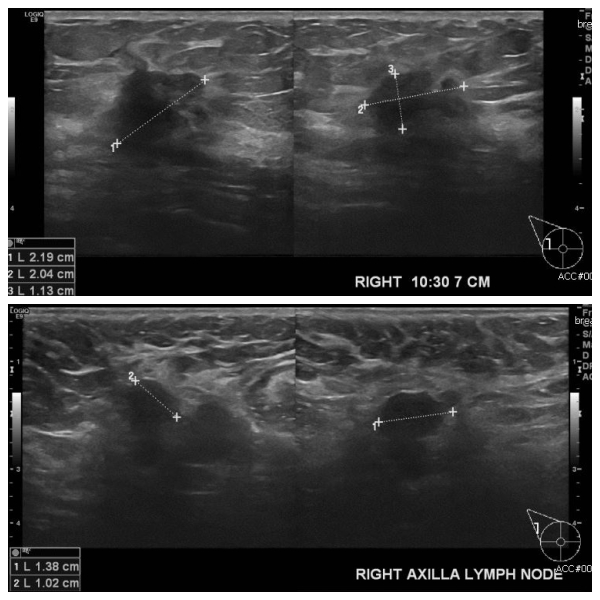

건강검진상 이상소견으로 내원하신 50대 여성분으로 본원 초음파 시행 후 우측 유방

10시 30분 방향에서 7cm 떨어진 거리의 혹 조직검사 시행하여 우측 침윤성 유관암

진단 되었으며, 우측 겨드랑이의 림프절 비대 부위 세포검사 시행하여 전이암 진단

되 었습니다.